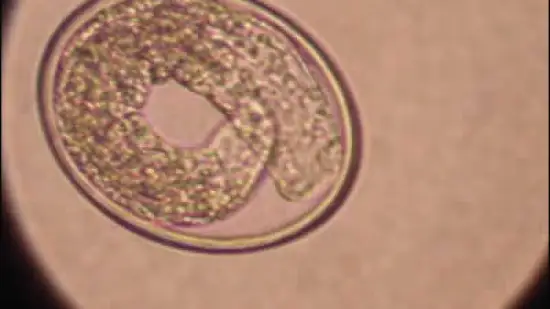

Questo uovo di parassita appartiene a: